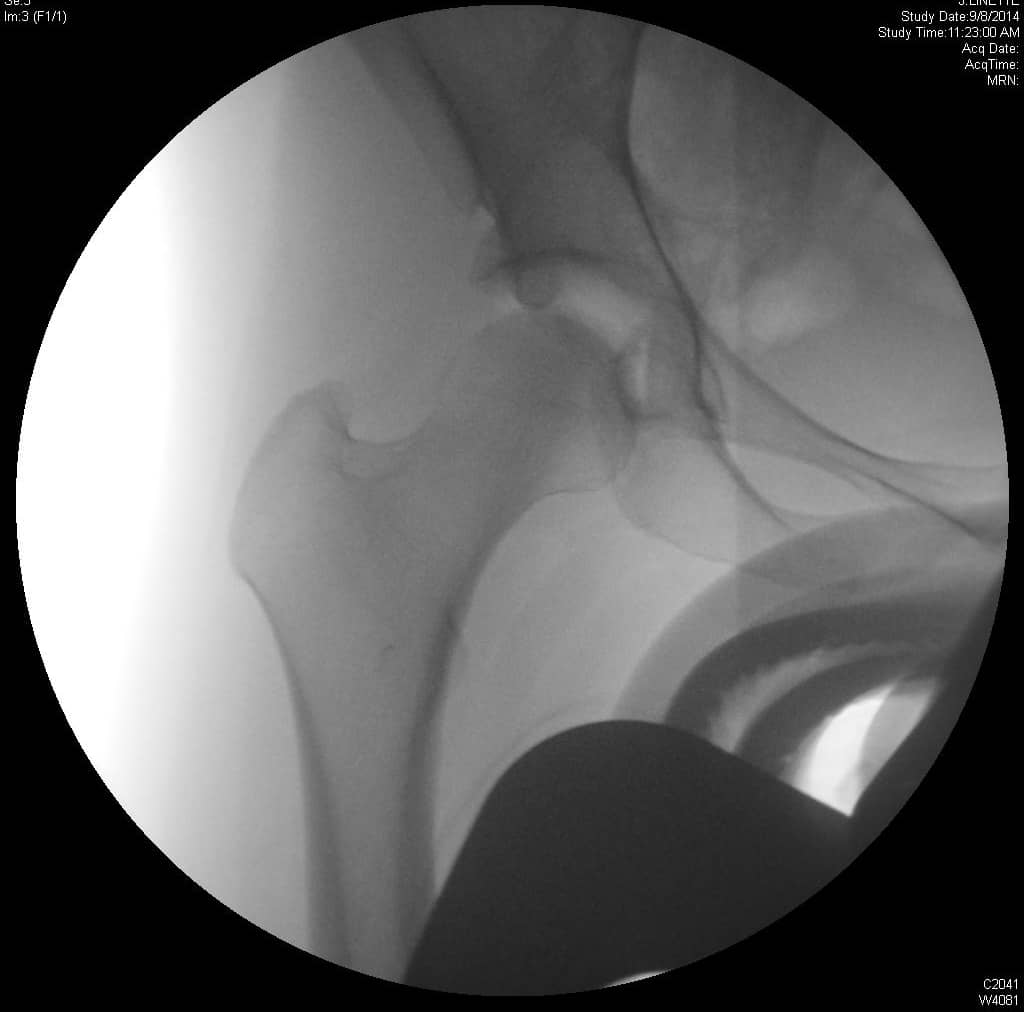

एक एपी श्रोणि दृश्य प्रभावित और अप्रभावित फेमोरा की तुलना की अनुमति देता है। यह सुनिश्चित करने के लिए समरूपता का आकलन करें कि एक सच्चा एपी दृश्य कैप्चर किया गया है। इसका आकलन यह जांचकर किया जा सकता है कि कोक्सीक्स सिम्फिसिस पबिस को ओवरलैप करता है, जिसमें दो संरचनाओं के बीच 2 सेमी से अधिक अलगाव नहीं होता है। संयुक्त स्थान में कमी और अपक्षयी परिवर्तनों के लिए संयुक्त का मूल्यांकन किया जाना चाहिए। अप्रभावित पक्ष के साथ एंटेरोलेटरल गर्दन समोच्च की तुलना करें। बेहतर गर्दन की शंकु की कमी सिर-गर्दन ऑफसेट को कम करने का संकेत देती है। एंटेरोसुपीरियर या पूर्ववर्ती सिर की सपाट या बढ़ी हुई त्रिज्या एक गोलाकार सिर को इंगित करती है। कई मापों का विश्लेषण किया जा सकता है:

- एफएआई के मूल्यांकन के लिए एक क्रॉस-टेबल पार्श्व दृश्य महत्वपूर्ण है, जिससे एंटेरोलेटरल फेमोरल गर्दन का दृश्य देखने की अनुमति मिलती है।

- अल्फा-कोण: ऊरु गर्दन की मध्य रेखा के साथ एक रेखा और ऊरु सिर के केंद्र से उस बिंदु तक एक रेखा के बीच बनता है जहां अतिरिक्त हड्डी सामान्य ऊरु सिर स्फेरिसिटी से विचलित होती है। 60 डिग्री से अधिक का कोण एफएआई को इंगित करता है।

- सिर-गर्दन ऑफसेट: ऊरु गर्दन के अनुदैर्ध्य अक्ष को विभाजित करने वाली रेखा से शुरू करें। एक समानांतर रेखा खींचें जो ऊरु गर्दन के पूर्ववर्ती पहलू के लिए स्पर्शरेखीय है और पूर्ववर्ती ऊरु सिर के समानांतर रेखा स्पर्शरेखा की दूरी को मापें। सामान्य दूरी 9 मिमी से अधिक है या सिर के व्यास का अनुपात 0.17 से अधिक है।